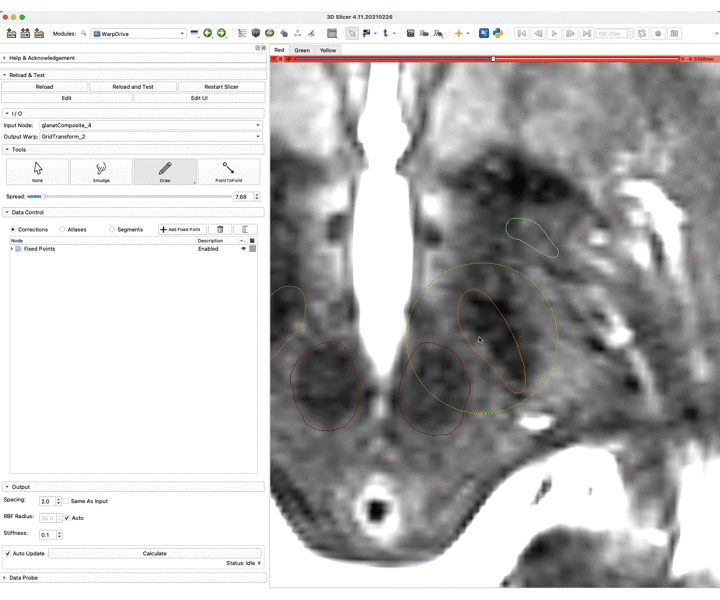

In order to achieve higher accuracy of the atlases registration to patient space, we rely on antsRegistration and we are also working on a module to manually fix for mismatches in the registration output.